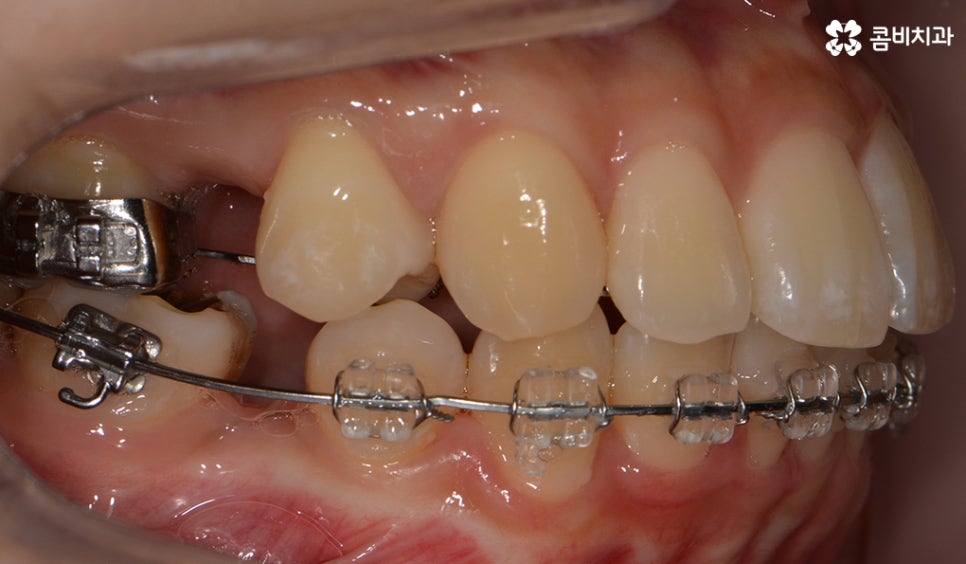

교정 치료 진행과정의 경과 모습

초기에 시술이 진행된 모습에 비해서 윗니가 가지런해졌고

돌출되었던 치아가 안쪽으로 많이 들어온 모습입니다.

발치를 했던 부위가 어딘지 잘 모를 정도로

윗니가 안쪽으로 들어와서 가지런하게

치열이 자리 잡고 있는 모습입니다.